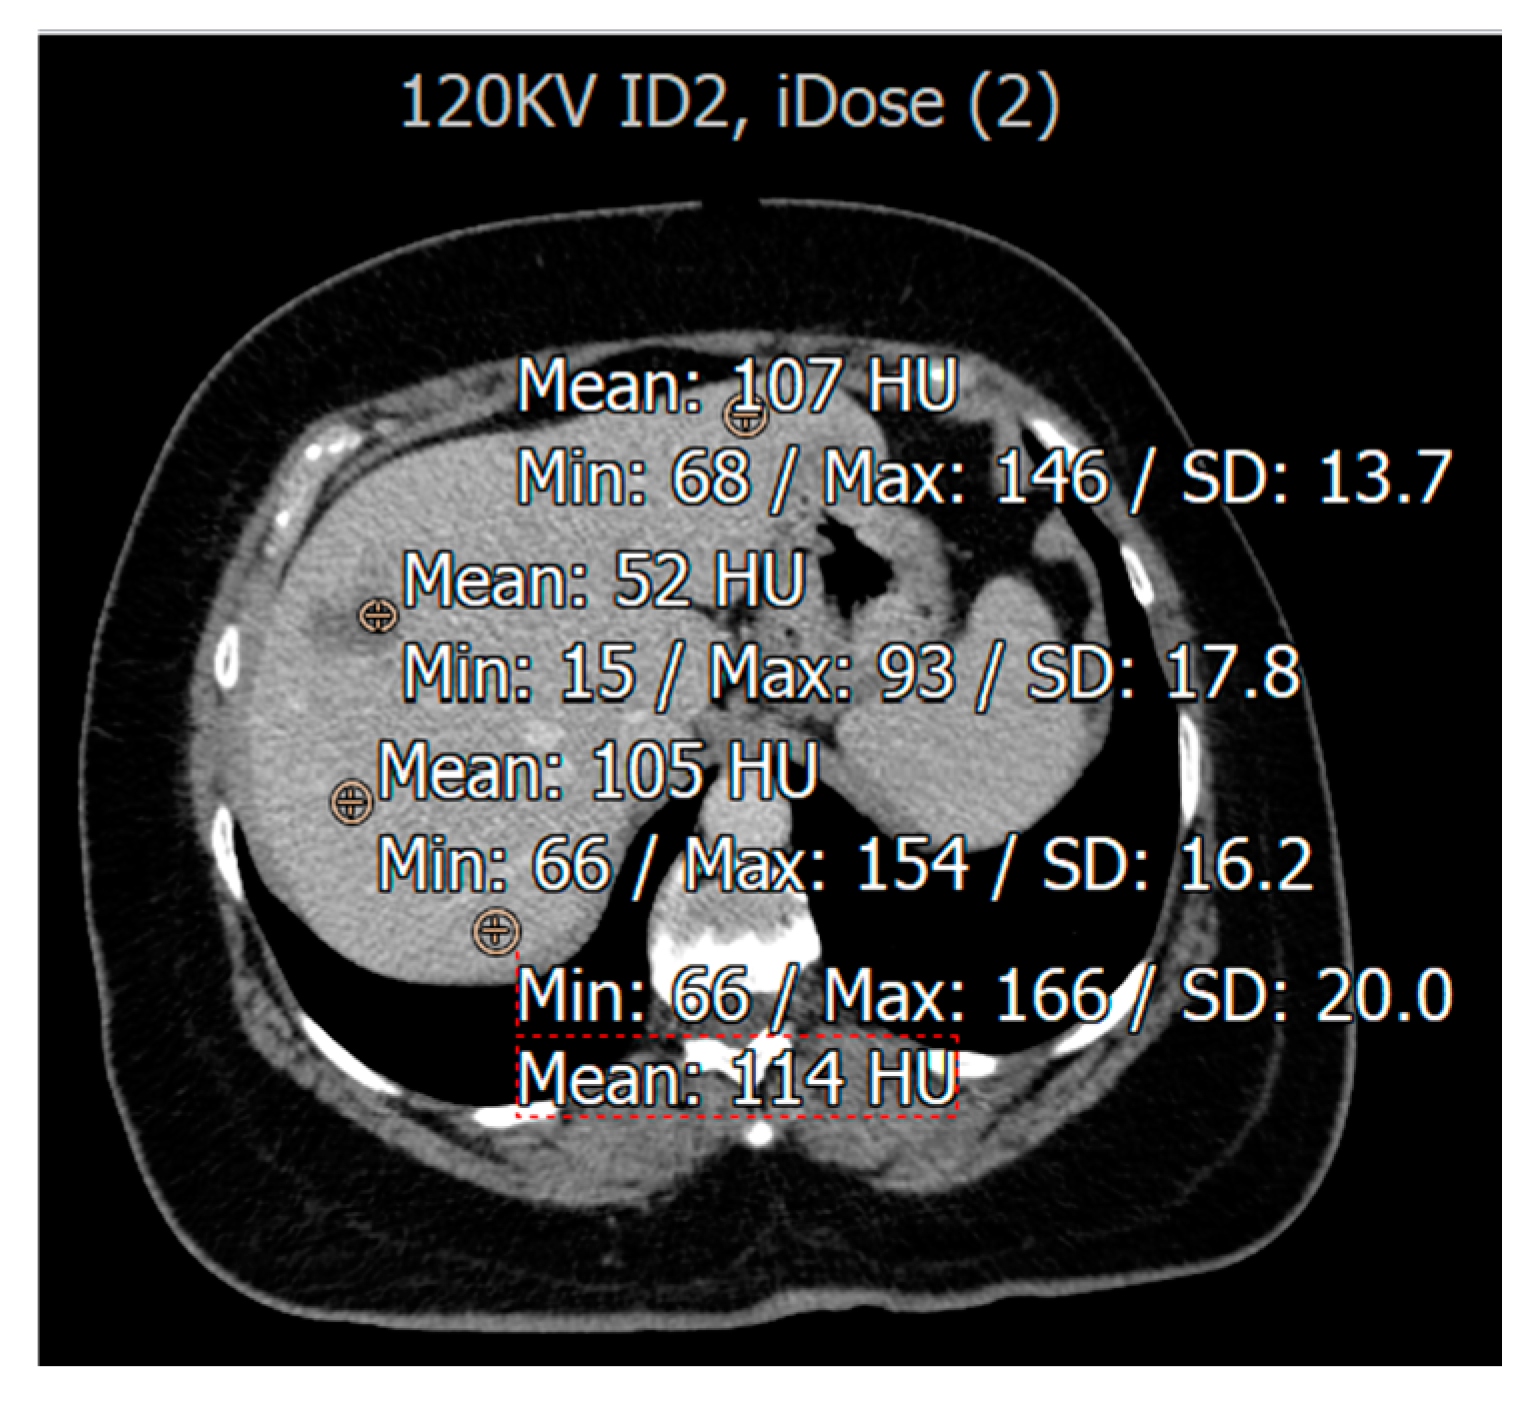

3.2. Evaluation for Patients with Fatty Liver Disease

Image Quality Assessment